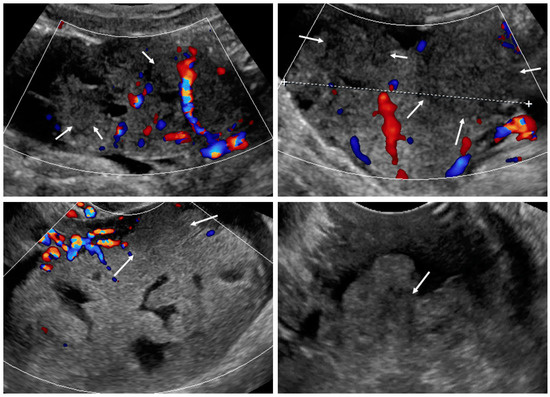

Figure 2.

Necrosis sign [7] in tumor solid portions. Arrows indicate area suspected for necrosis. White dotted line is a measurement of the tumor.